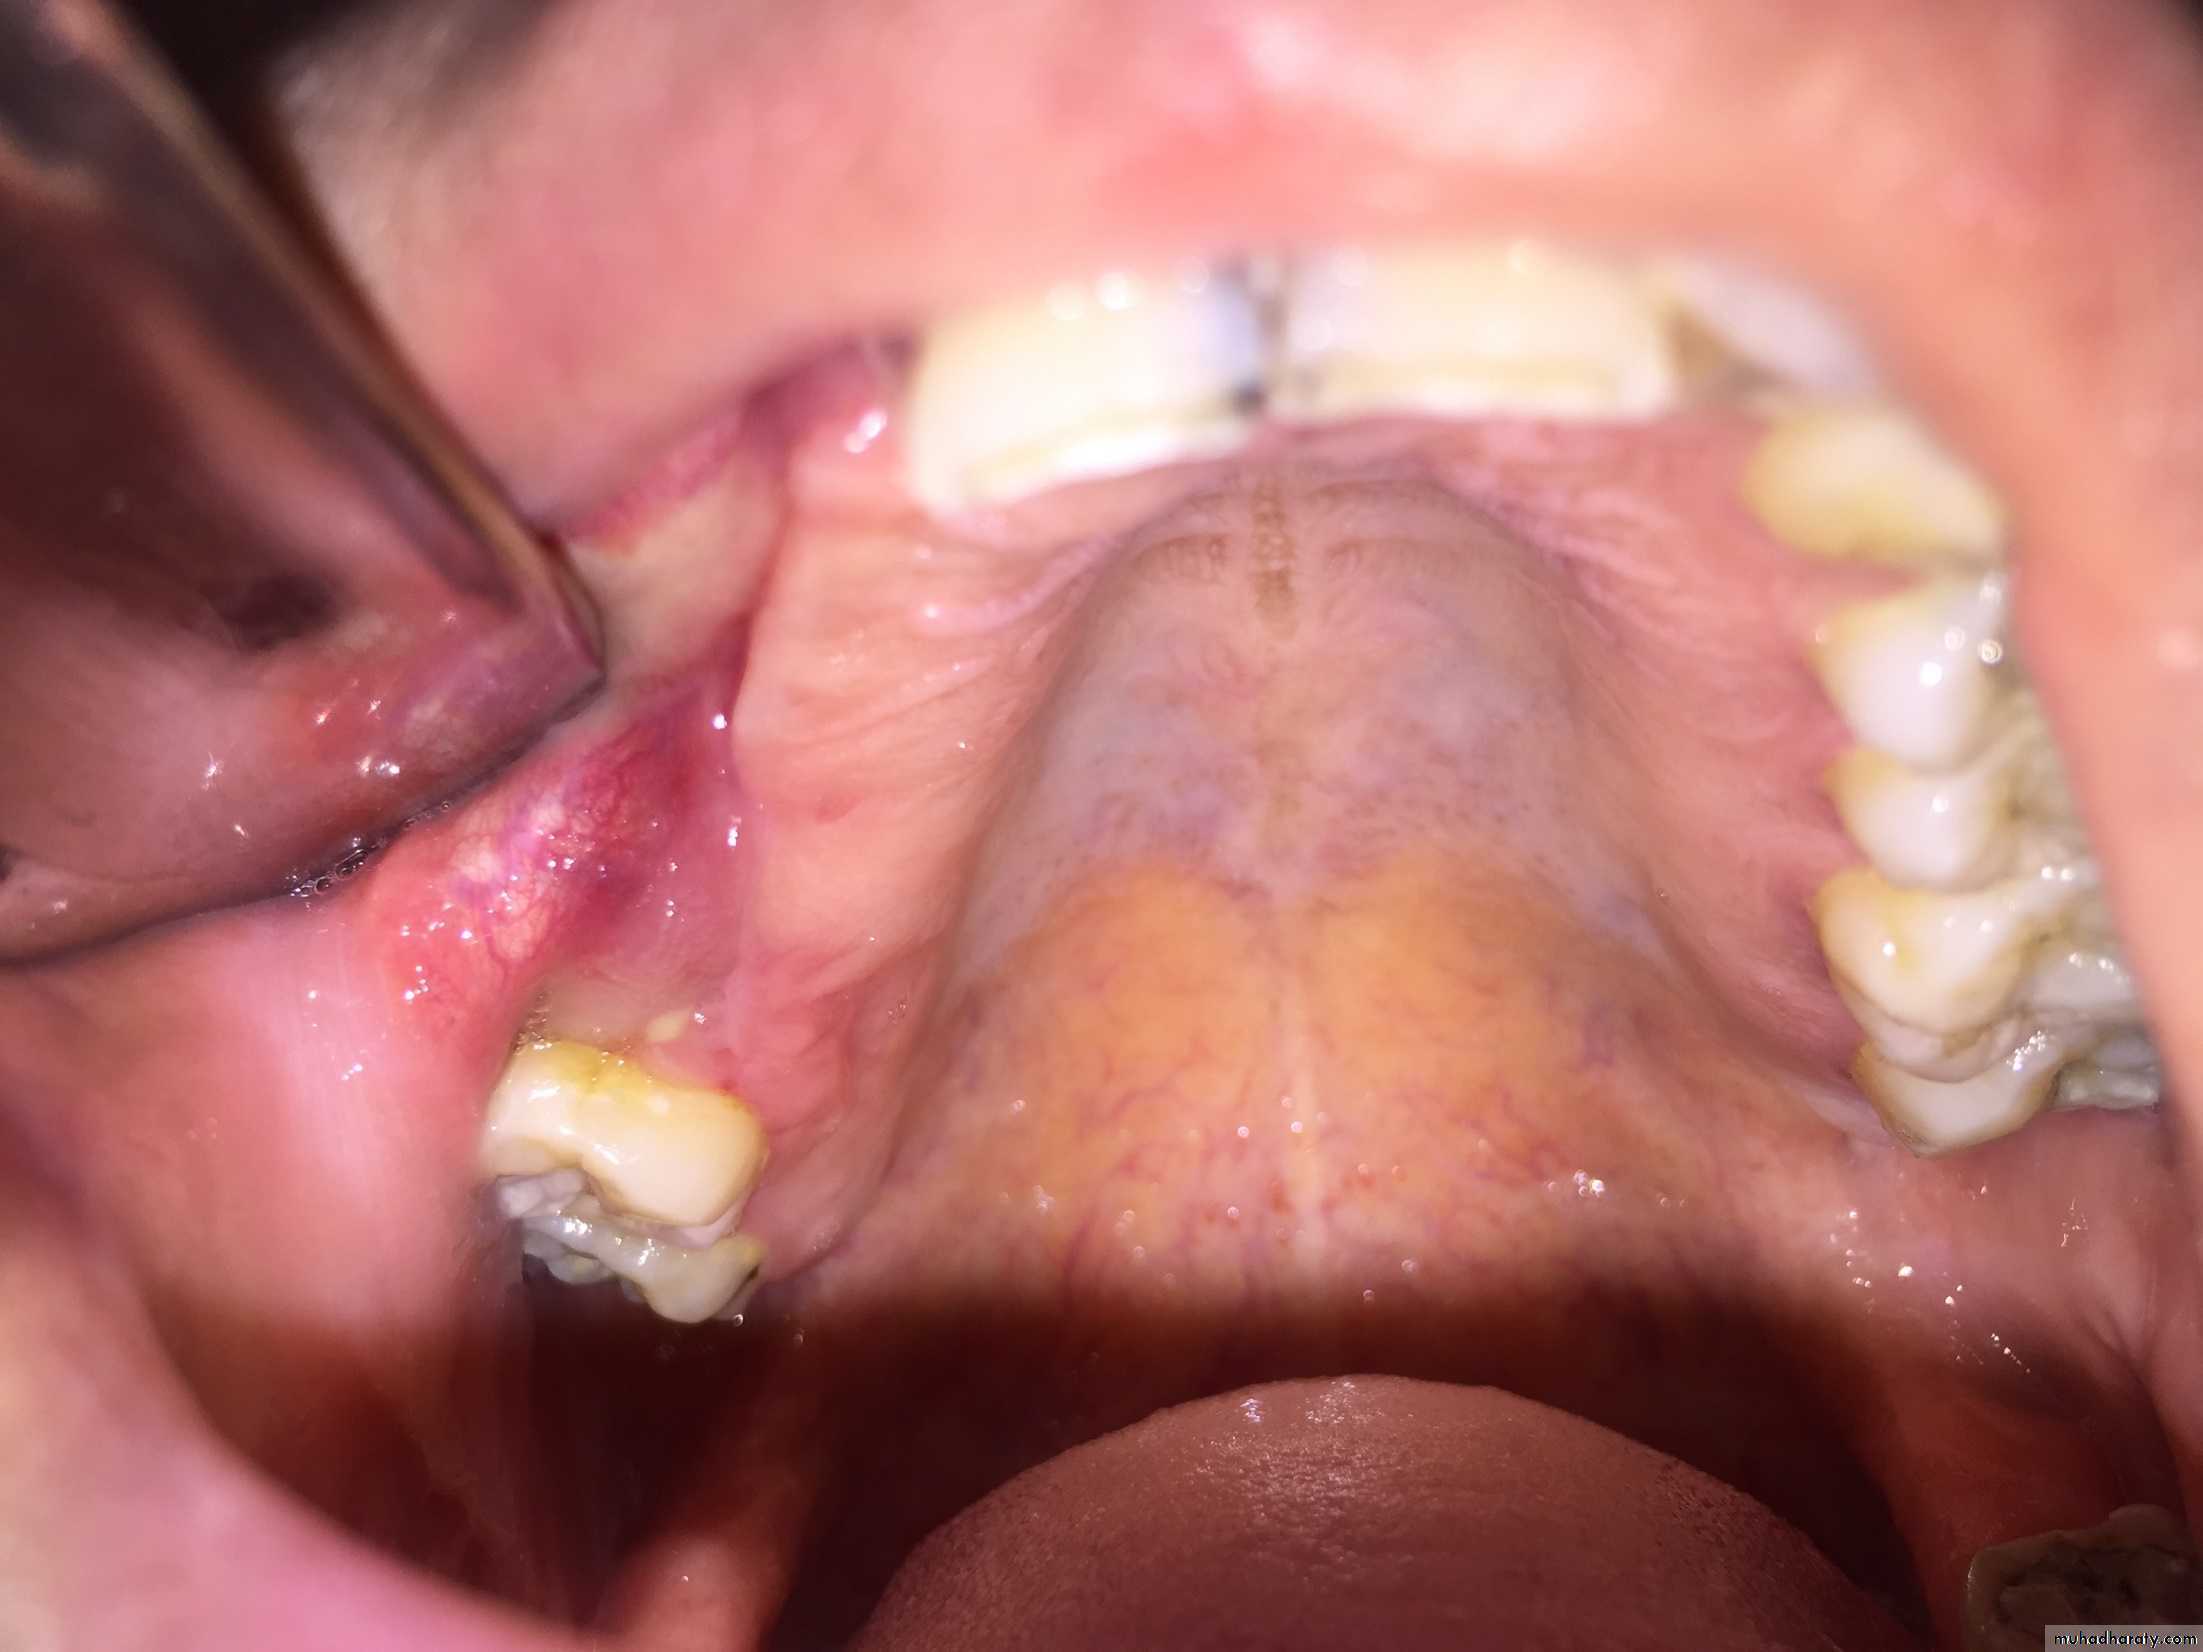

Ameloblastoma:-

It is a tumor arising from embryonal cells of developing teeth. Although most forms of this tumor simulate other slow-growing benign tumors some can develop malignant tendencies.Patient may have few subjective symptoms during tumor growth. Enlargement of the tumor may expand the buccal, lingual or palatal bone plates. Tooth may be loosen and pressure symptoms may occur.

Raioraghical examination may demonstrate unlocular or multilocular types. Unilocular ameloblastomas may be confused with benign cysts. The tumors frequently absorbs the alveolus surrounding ,the roots of teeth and may absorb root ends.

Ameloblastoma grow by extension into adjacent tissues and may perforate the investing bone. A biopsy should precede treatment since

these tumors frequently present with individual characteristics.